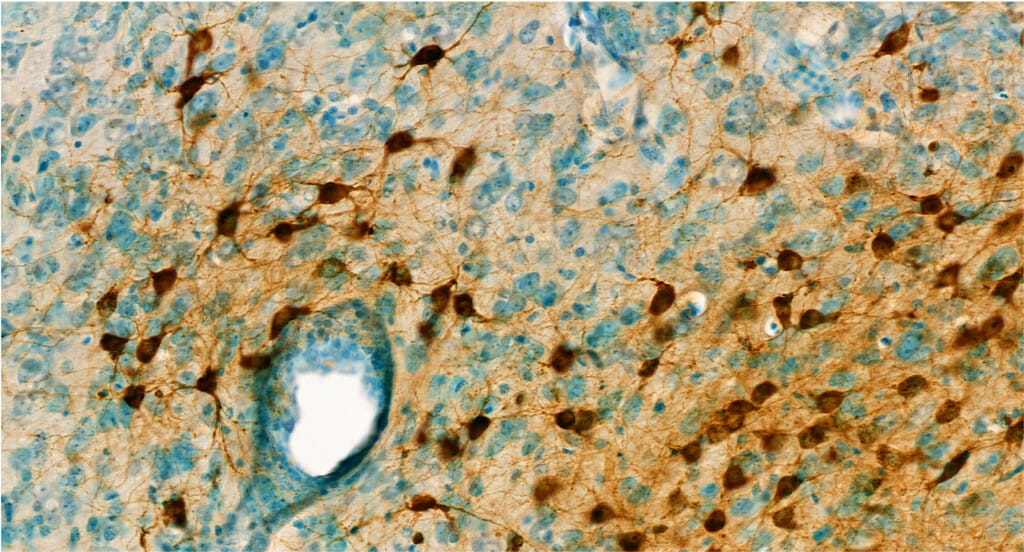

This image shows a mouse brain cells infected with Venezuelan equine encephalitis virus, which is one of two viruses that cause encephalitis that are neutralized by a compound discovered by UW–Madison researchers. IMAGE COURTESY OF DR. YI XUE A new antiviral compound designed and synthesized by researchers at the University of Wisconsin–Madison’s School of Pharmacy is highly effective in mice against two types of devastating encephalitis viruses that are harmful to humans.